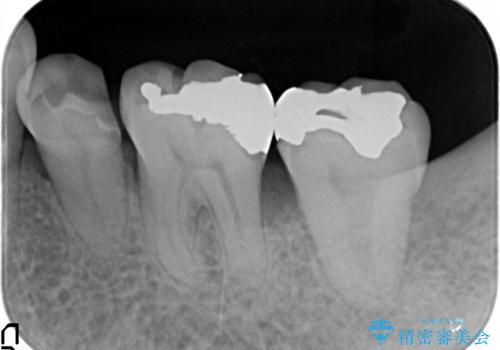

歯周病再生治療と歯周ポケット除去 歯周外科手術

- 他院で歯周病を指摘され、様子見ではなく根本的な治療はないか?とご相談に来院されました。

重度の歯周病で再生療法の適応ではない最後方臼歯は抜去行い、インプラント治療、

がたつきの強い天然歯を矯正治療で整えたのち、再生治療、歯周ポケットを除去する歯周外科手術を行いました。

再生療法を行ったことで、抜歯をされてもおかしくなかった歯を、残すことができました。